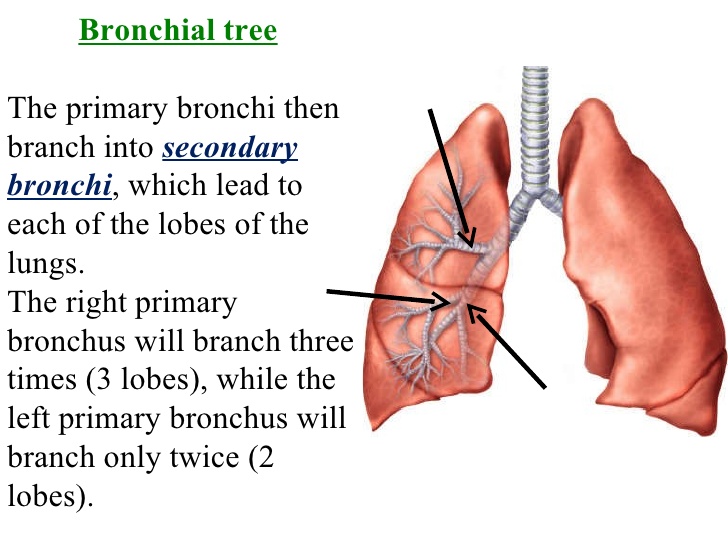

(4) Bronchi:

The trachea leads into the bronchi, each bronchus leads into a lung.

(5) Lungs: each bronchus leads into a lung. Inside the lungs are tiny tubes called bronchioles. The bronchioles branch again into alveoli.

(4) Bronchi:

The trachea leads into the bronchi, each bronchus leads into a lung.

(5) Lungs: each bronchus leads into a lung. Inside the lungs are tiny tubes called bronchioles. The bronchioles branch again into alveoli.